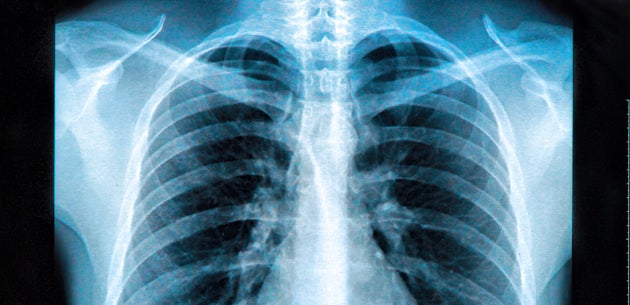

Polmoni riempiti con un muco appiccicoso che impedisce di respirare perché non c'è spazio per l'aria è quanto rivelano le immagini ai raggi x dei pazienti affetti da coronavirusMentre il Covid19 continua a diffondersi in tutto il mondo e il bollettino delle vittime aumenta (al momento sono oltre 4500 i decessi), i medici stanno iniziando a capire sempre più come il nuovo virus colpisce. Polmoni riempiti con un muco appiccicoso che impedisce di respirare perché non c'è spazio per l'aria è quanto rivelano le immagini ai raggi x dei pazienti affetti da coronavirusMentre il. Polmoni pieni di muco ecco come uccide il coronavirus Redazione L'Occhio 12 Marzo 12 2 minutes read Come uccide il coronavirus?.

Polmoni riempiti con un muco appiccicoso che impedisce di respirare perché non c'è spazio per l'aria è quanto rivelano le immagini ai raggi x dei pazienti affetti da coronavirusMentre il Covid19 continua a diffondersi in tutto il mondo e il bollettino delle vittime aumenta (al momento sono oltre 4500 i decessi), i medici stanno iniziando a capire sempre più come il nuovo virus colpisce. Il dolore toracico di tipo pleurico, dovuto a versamento pleurico, può scomparire all’accumulo di liquido Grandi quantità di liquido possono ostacolare l’espansione di uno o di entrambi i polmoni alla respirazione, con conseguente respiro affannoso. Infatti, la presenza insolita di fluidi compromette la funzione svolta dagli alveoli durante la respirazione.

La polmonite è una malattia dei polmoni e più in generale del sistema respiratorio, caratterizzata dall'infiammazione degli alveoli polmonari, i quali, riempiendosi di liquido, ostacolano la funzione respiratoria, solitamente causata da un'infezione dovuta a virus, batteri e altri microrganismi e meno frequentemente come conseguenza della somministrazione di alcuni farmaci o di altre. Polmoni riempiti con un muco appiccicoso che impedisce di respirare perché non c’è spazio per l’aria è quanto rivelano le immagini ai raggi x dei pazienti affetti da coronavirus Mentre il Covid19 continua a diffondersi in tutto il mondo e il bollettino delle vittime aumenta (al momento sono oltre 4500 i decessi), i medici stanno. Segni di liquido nei polmoni di un gatto I polmoni del tuo gatto possono essere pieni di liquido per una serie di motivi, ma l'apprendimento dei segni può aiutarti ad ottenere aiuto per il tuo animale prima che si verifichino gravi conseguenze per la salute I polmoni dei gatti ossigenano il sangue e rimuovono l'anidride carbonica allo stesso modo degli umani.